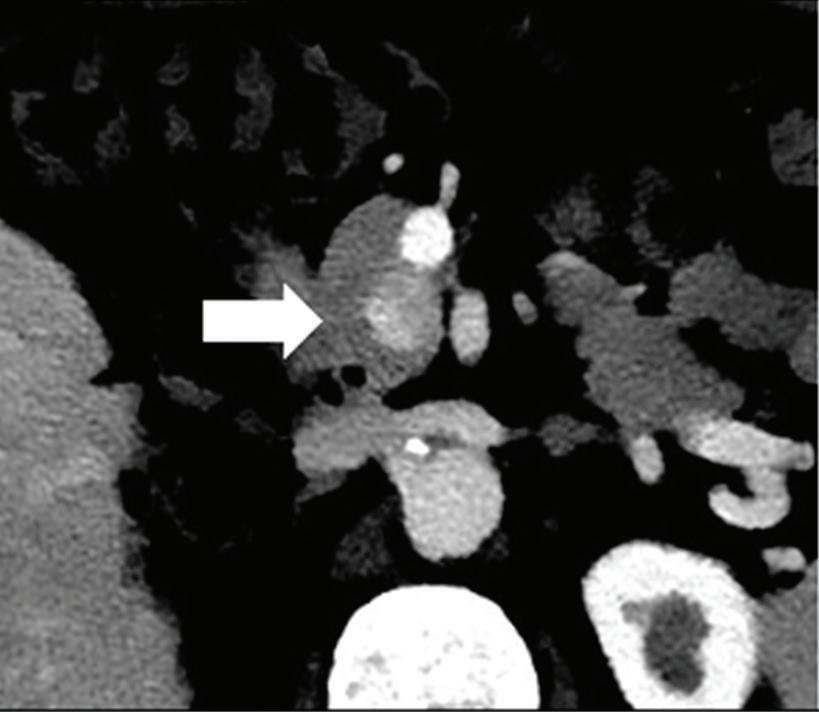

Renal and adrenal gland tumors. Contrast-enhanced-DECT images are particularly useful for the characterization of incidental renal or supra-renal lesions and for their follow-up, without the need of conventional unenhanced acquisition, translating into achieving a 30% mean dose savings for triphasic and up to 50% for biphasic renal protocols in daily clinical practice.17 It is also very useful in depicting hypervascular renal cell carcinoma metastasis in the liver or other sites, such as in the peritoneum and bowel wall (Figures 2 and 3).

Effectiveness of spectral CT imaging for detection of hypervascular liver metastases. A small hypervascular metastasis (arrow) from renal cell carcinoma. (a) Axial contrast-enhanced conventional CT image obtained in the arterial phase, corresponding (b) monoenergetic 50 keV, and (c) Z effective image.

Effectiveness of spectral CT imaging for detection of a peritoneal implant from a renal cell carcinoma invading the bowel wall (arrow). (a) Coronal contrast-enhanced conventional CT image obtained in the arterial phase, corresponding (b) Z effective, (c) monoenergetic 50 keV, and (d) iodine-density image.